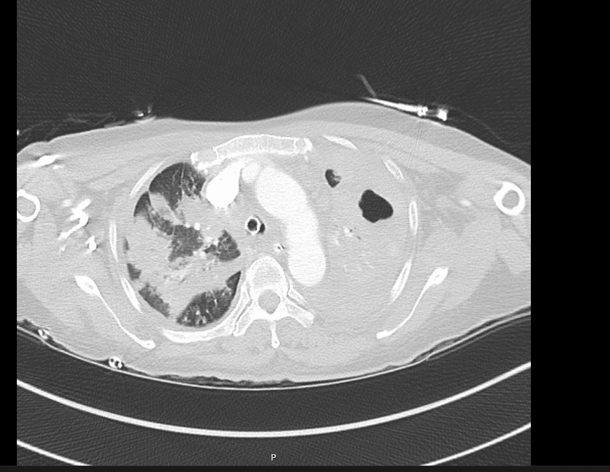

CASE 5 –A 57-year-old woman presented to the emergency department with fevers, cough and night sweats and recent weight loss. She arrived in Australia from Philippines 5 days previously. In the ED she had significant respiratory distress requiring high flow oxygen and subsequent intubation and ventilation as her respiratory failure progressed.

EXPLANATION -There is diffuse bilateral consolidation more prominent in the upper lobes.

There is left upper lobe cavitation. Bilaterally there are pleural effusions.